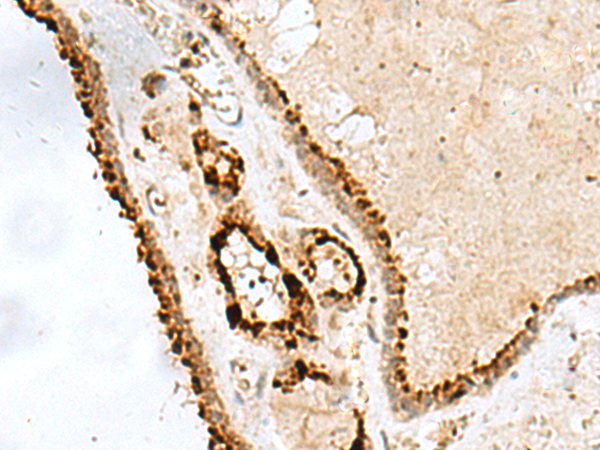

IHC positive control:

Human thyroid cancer

IHC Recommend dilution:

20-100